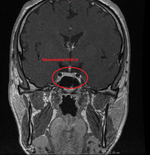

Weil ich Angst habe das mein Hirn von Schwermetalle geschädigt ist, und die Radiologie es nicht sieht ( weil die Microweiße Punkte im Hirn keiner Bedeutung zuweisen, diese sich aber über kurz oder Lang vergrößern können) habe ich die CD's der beiden MRT's aus den letzten beiden Jahren angefordert und möchte mittels Daunderers Bildmaterial mein Hirn mal vergleichen. Vielleicht erkenne ich ja Auffälligkeiten.

Um ein Microadenom auszuschließen erfolgt MRT 3 in den nächsten 4-8 Wochen. Dabei begleitet mich ein Neurologe der mir dann hoffentlich auch mal Diazepam verschreibt. Ich möchte das Zeug unbedingt testen und in wirklich schwierigen Zeiten so wie gestern und heute einfach mal 2 Tage nehmen um ne Pause von meinen Rückenproblemen zu haben. Plan sind 2-4 Einnahmezyklen pro Monat jeweils über 2 Tage um keine Abhängigkeit zu riskieren. Die Nebenwirkungen sind deutlich milder als bei Ortoton.